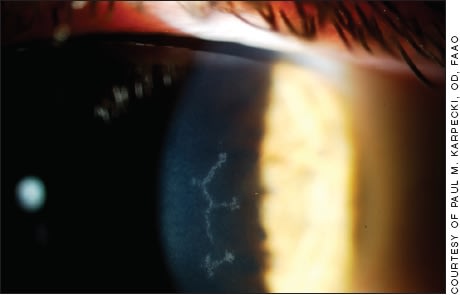

Herpes simplex virus dendritic ulcer.